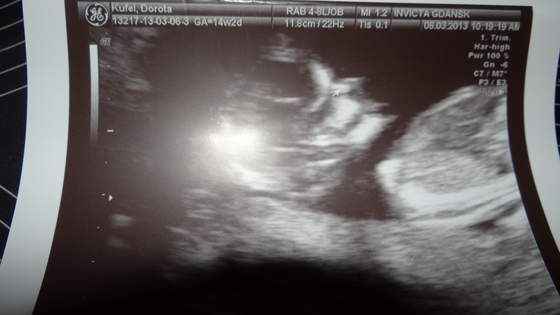

Jadźka ty się nie przejmuj, ja też mam na razie łożysko na przedniej ścianie, ale to się podobno może szybko zmienić, więc jest szansa, że szybciutko ruchy dziecka poczujesz ;-). Żeby było śmieszniej ja jestem na 100% przekonana że już pierwsze ruchy czułam w nocy i mimo że mój mąż uparcie twierdzi że głupia jestem i na pewno mi się zdawało (14 tyg.) ja wiem swoje

.